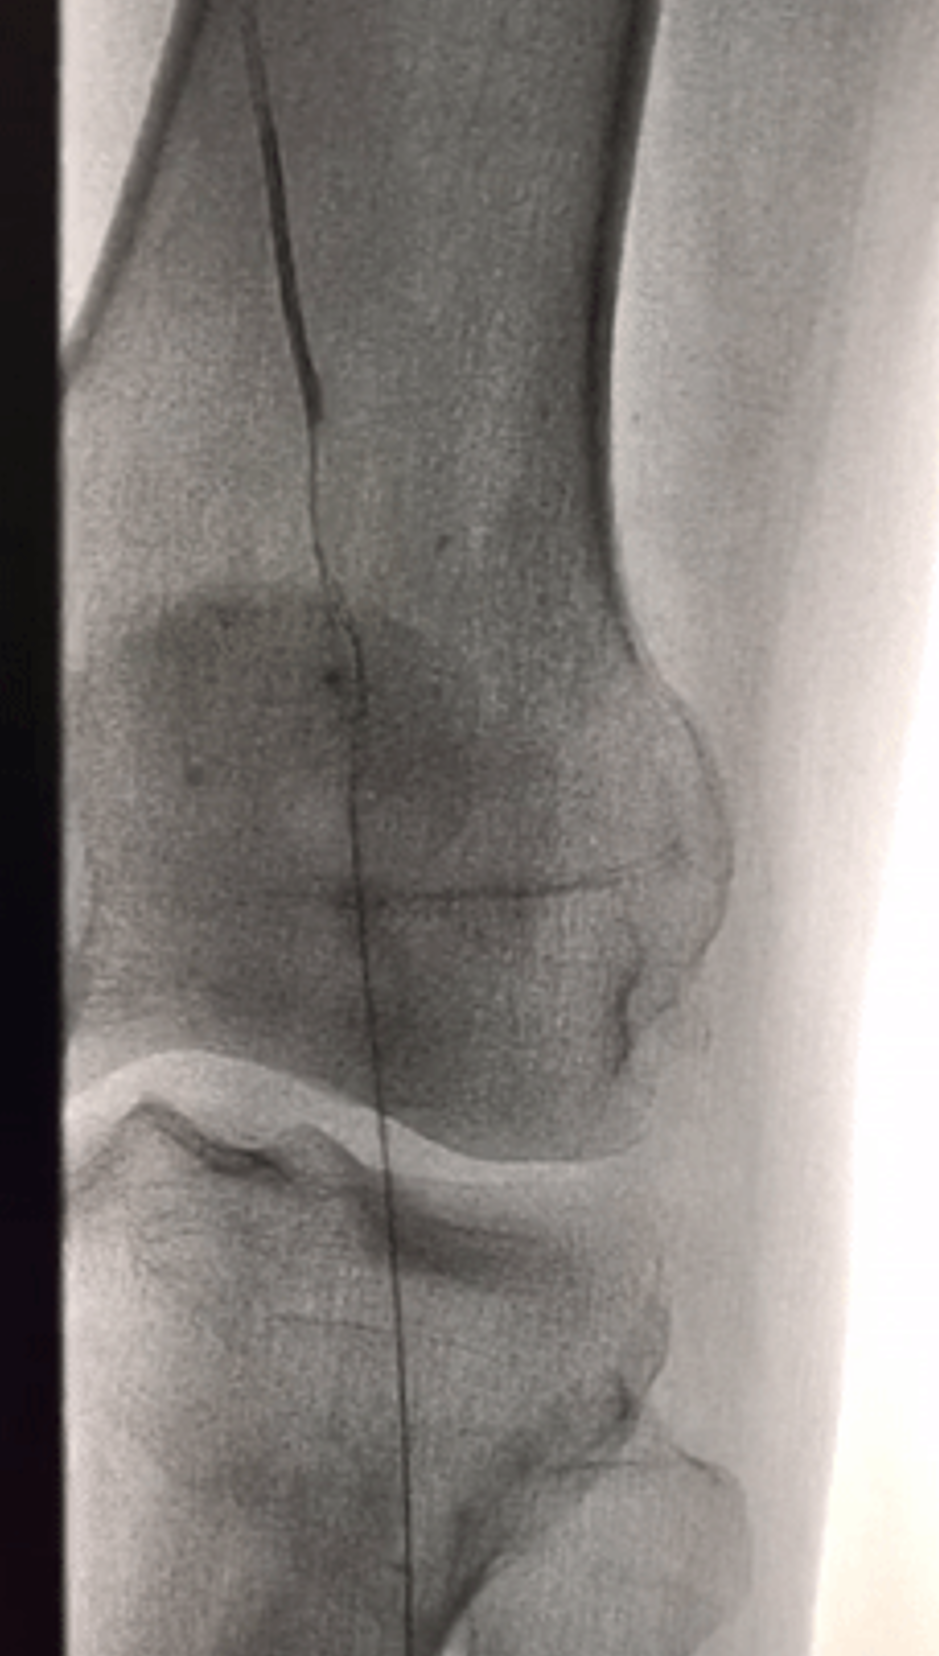

Case 1:胫前动脉长段闭塞,导丝成袢后通过,IVUS显示大部分位于假腔,但血流仍可维持。

Case 2:类似病变,成袢后导丝全程位于真腔,仅局部转弯处有夹层形成。